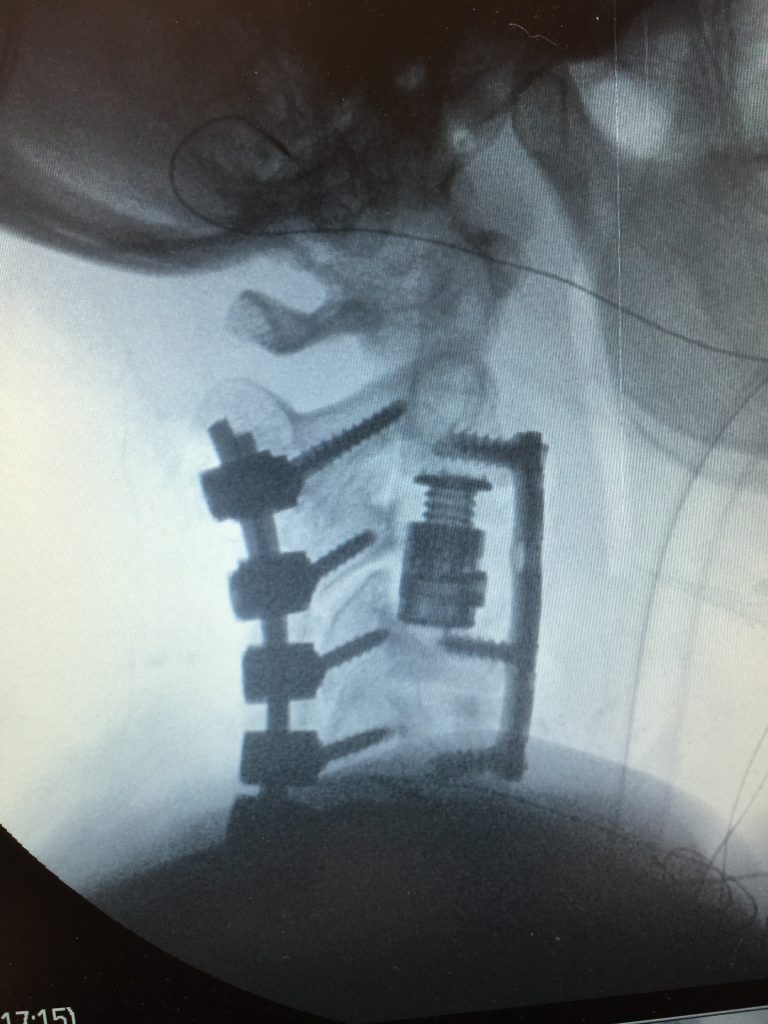

A corpectomy is a surgical procedure to remove a damaged vertebra from your spine to alleviate pressure on your spinal cord or nerves. It is very similar to a discectomy, but used in cases when the damage is more severe.

During a corpectomy, an incision is made in the front of the neck, and the surgeon performs a discectomy at both ends of the vertebra to be removed. The damaged vertebra is then removed, and a bone graft or an artificial cage is put in its place and fused with the surrounding bones. A corpectomy is sometimes used to treat multi-level spinal stenosis in which bone spurs compress the spinal canal. Corpectomy surgeries are more extensive than discectomies and carry greater risks, and are recommended only in the event of significant problems related to the spine.